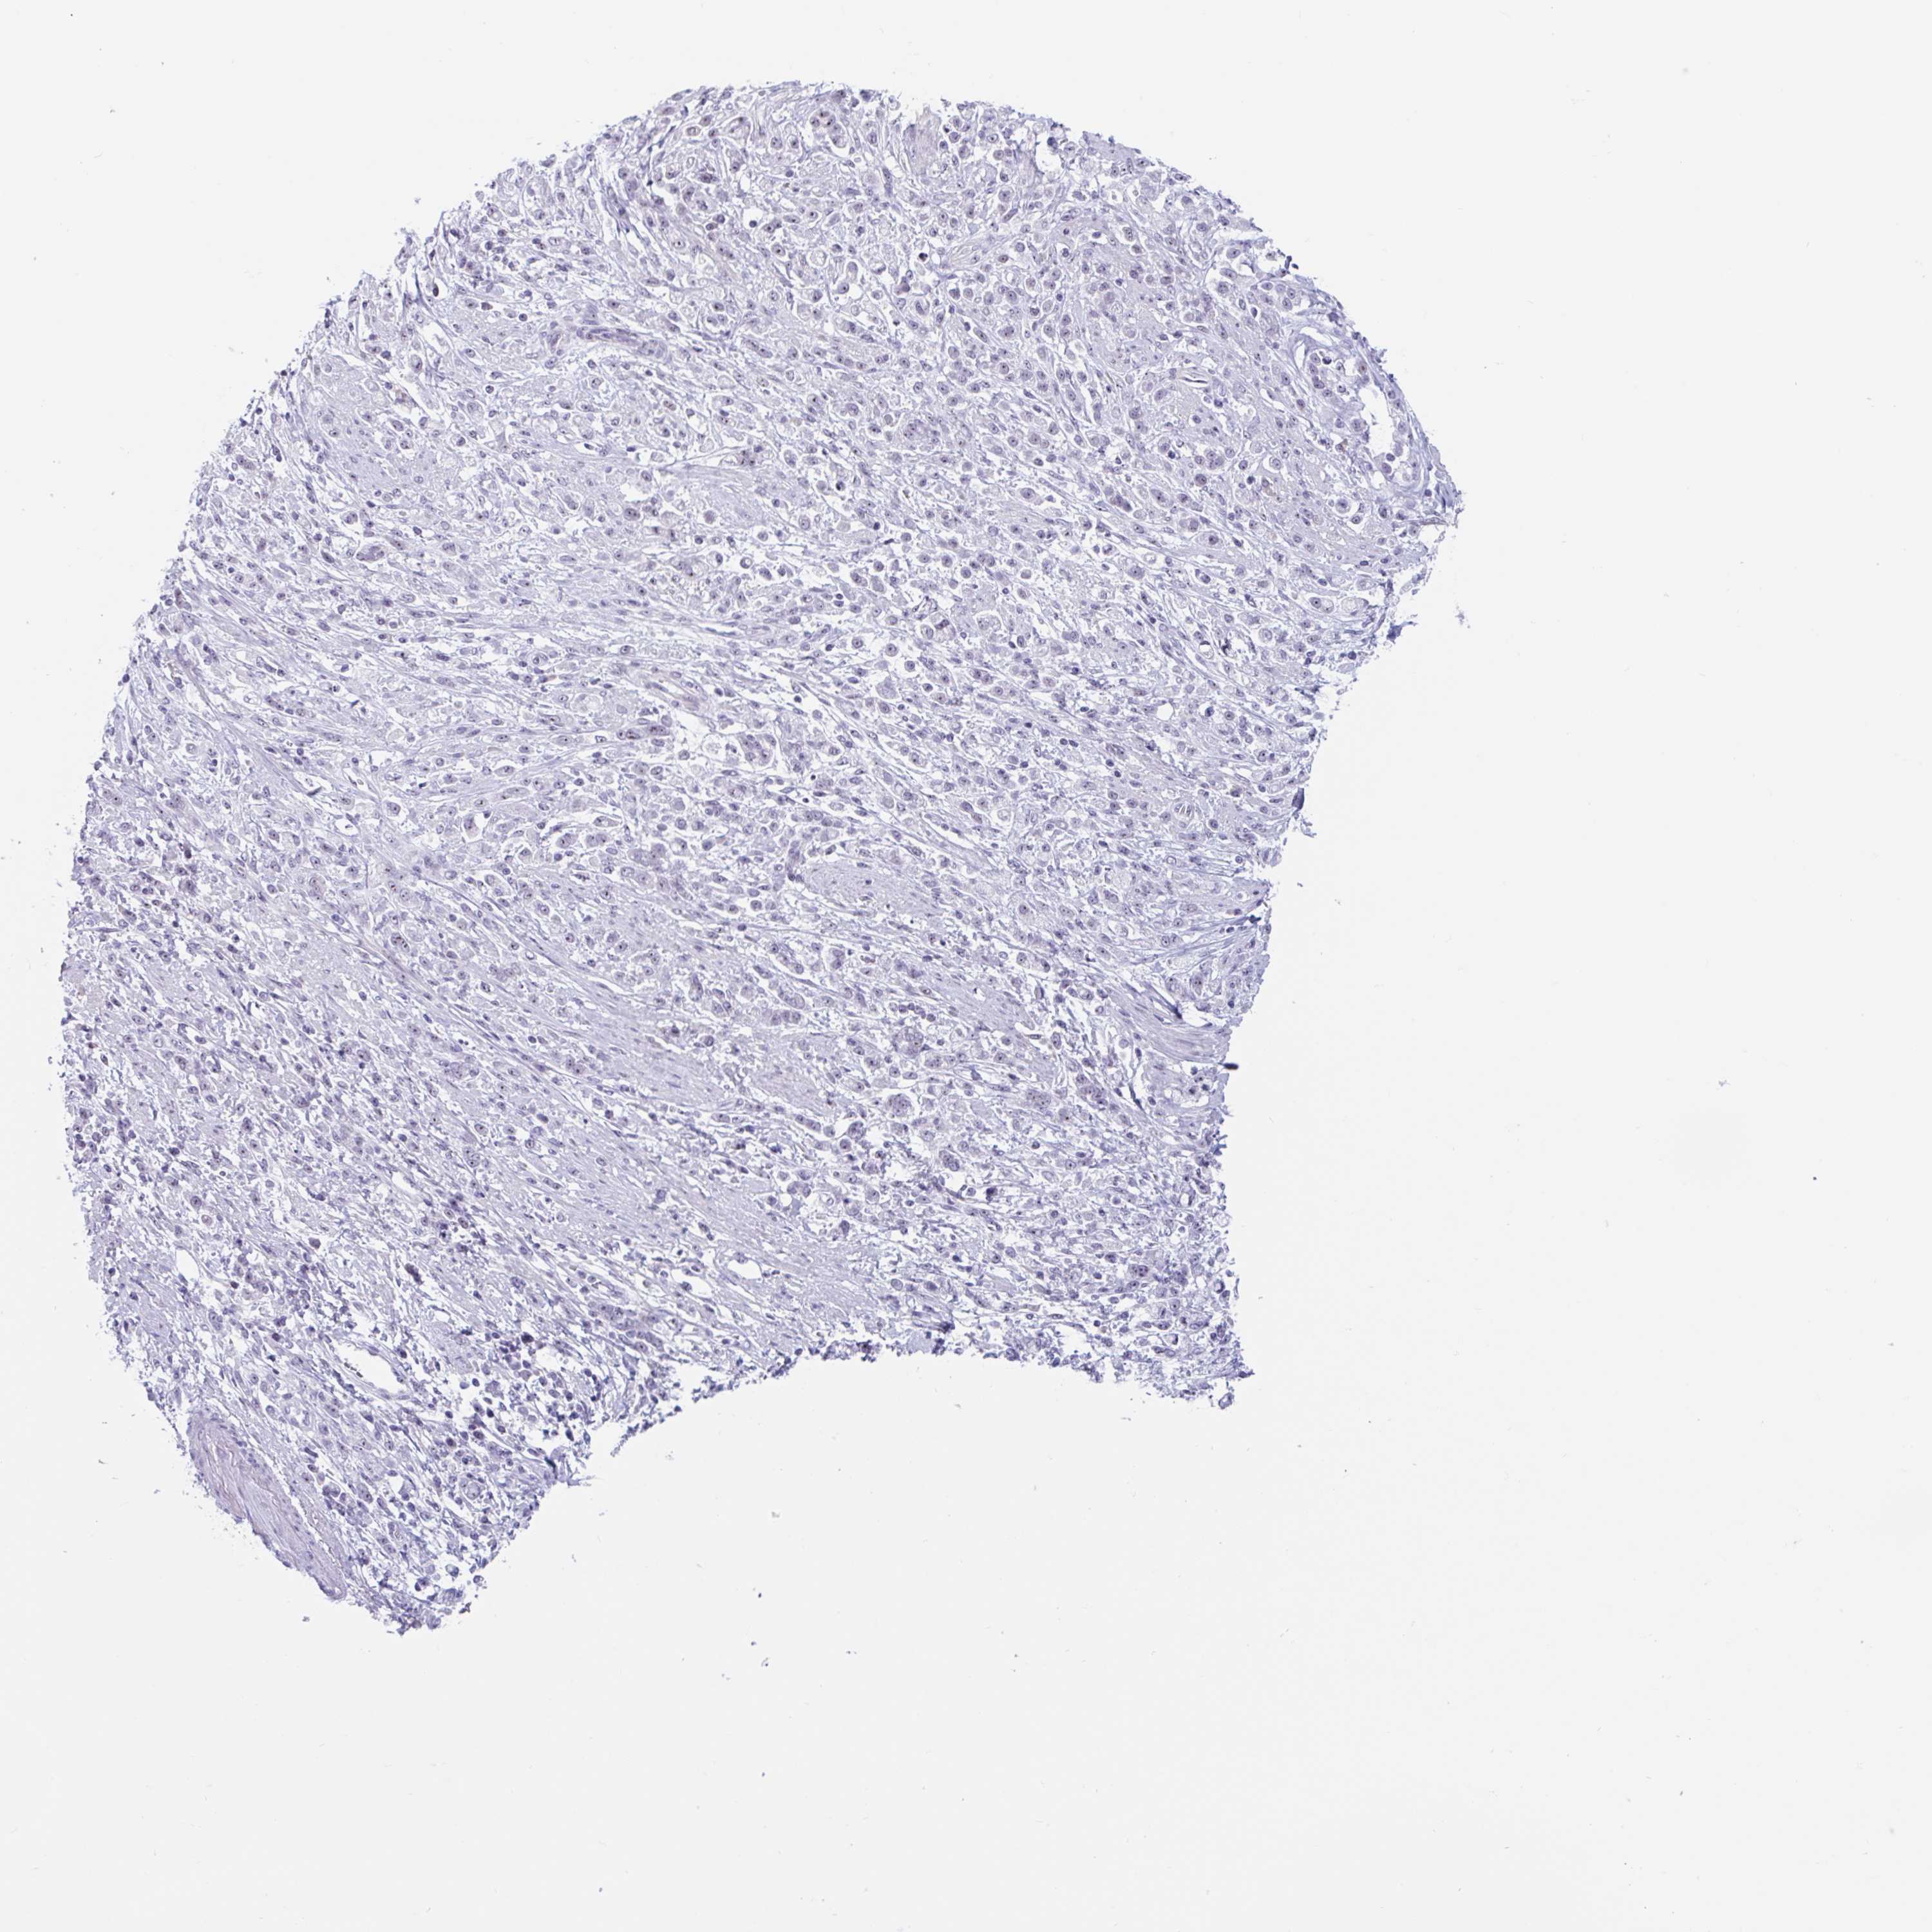

STOMACH CANCER - Protein expressioni

A mouse-over function shows sample information and annotation data. Click on an image to view it in a full screen mode. Samples can be filtered based on level of antibody staining by selecting one or several of the following categories: high, medium, low and not detected. The assay and annotation is described here.

Note that samples used for immunohistochemistry by the Human Protein Atlas do not correspond to samples in the TCGA dataset.

Antibody stainingi

Antibody staining in the annotated cell types in the current human tissue is reported as not detected, low, medium, or high, based on conventional immunohistochemistry profiling in selected tissues. This score is based on the combination of the staining intensity and fraction of stained cells.

Each image is clickable and will lead to virtual microscopy that enables deeper exploration of all samples and also displays staining intensity scores, fraction scores and subcellular localization as well as patient and tissue information for each sample.

Antibody HPA051671

Antibody HPA053556

Staining

High

Medium

Low

Not detected

Adenocarcinoma, NOS